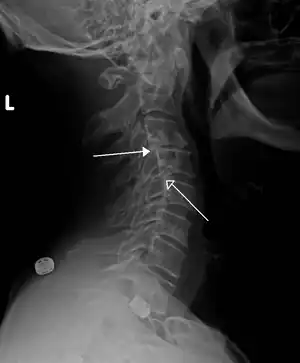

X-ray of measurement of spondylolisthesis at the lumbosacral joint, being 25% in this example.

X-ray picture of a grade 1 isthmic anterolisthesis at L4-5